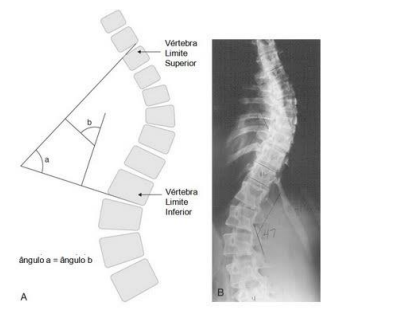

O ângulo Cobb é a medida mais utilizada para diagnosticar escoliose e, consequentemente, acompanhar

o progresso da deformidade da coluna vertebral. A imagem seguinte demonstra que existe:

Fonte: https://fisioterapeutico.wordpress.com/2010/11/10/o-angulo-de-cobb/